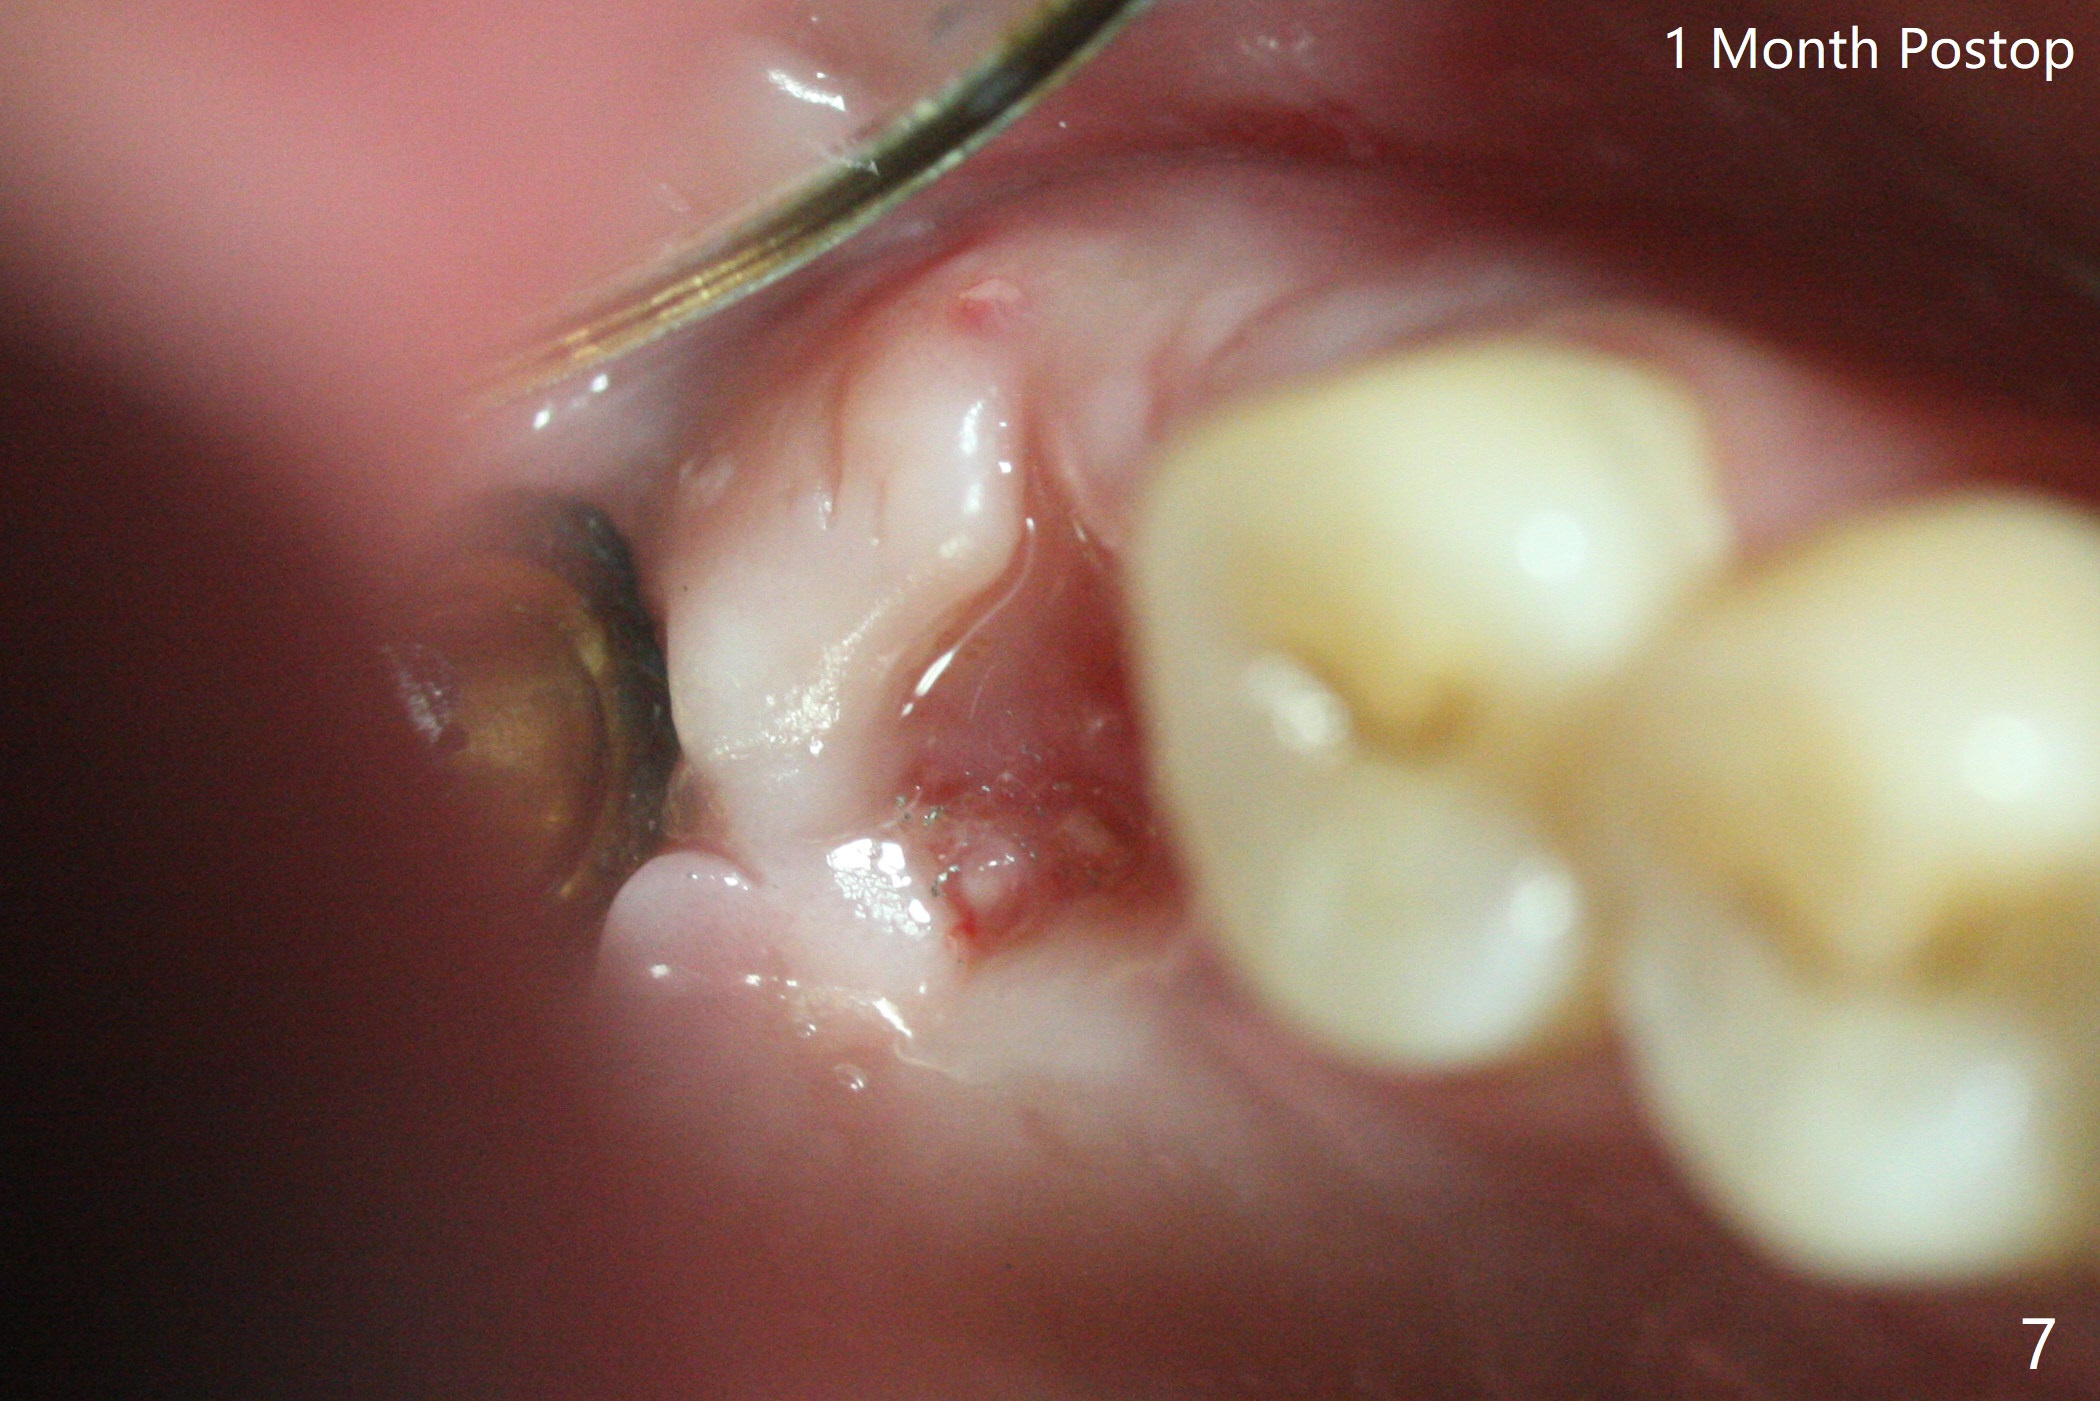

根管治疗后完全裂开(图四),需要拔除植骨。术后一个月,角化龈基本保持原位。由于松弛缝合,角化龈有可能增加~6毫米(图七)。